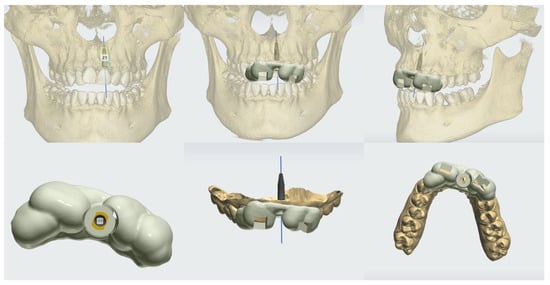

3.1. Case No. 1

3.2. Case No. 2